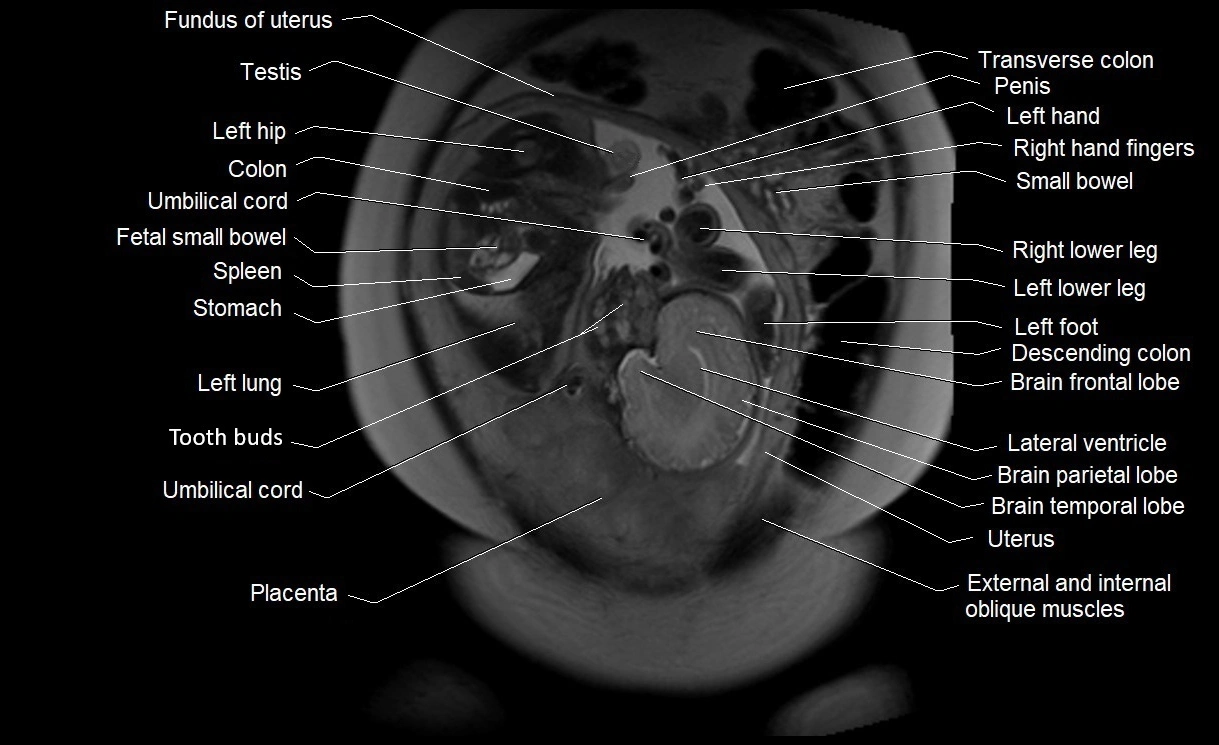

MRI Appearance

T2 HASTE (T2 GRE):

• Amniotic fluid shows very bright hyperintense signal

• Provides natural contrast against fetus and placenta

• Small particles (vernix) may appear as scattered hypointense foci within bright fluid

MRI image

image